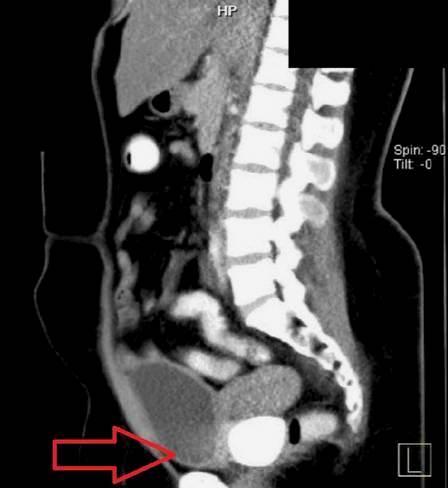

Um exame simples, porém, levantou sinais de que algo estava obstruindo a vagina. Exames de imagem a seguir mostraram duas pedras "sólidas e lisas" dentro da área pélvica.

Médicos descobrem pedras ‘gigantes’ na vacina de pacienteExame detecta pedras vaginais em paciente na Indonésia – Foto: Reprodução/Urology Case Reports

Medindo 3,6cm por 5cm e 5cm por 5,8cm, as pedras retiradas eram do tamanho de duas bolas de pingue-pongue. Uma estava presa à parede da bexiga, enquanto a outro estava presa à parede do reto.